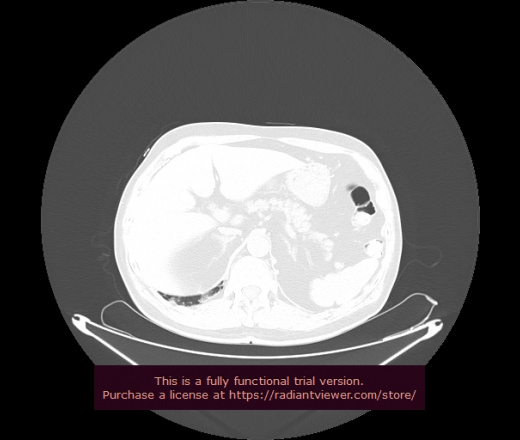

Уважаемые коллеги, если имеется интерес, сможете ли Вы спрогнозировать дальнейшее +-одинаковое течение процесса у 4 данных разных пациентов? Зацепиться где-то можно очень просто, где-то нельзя.